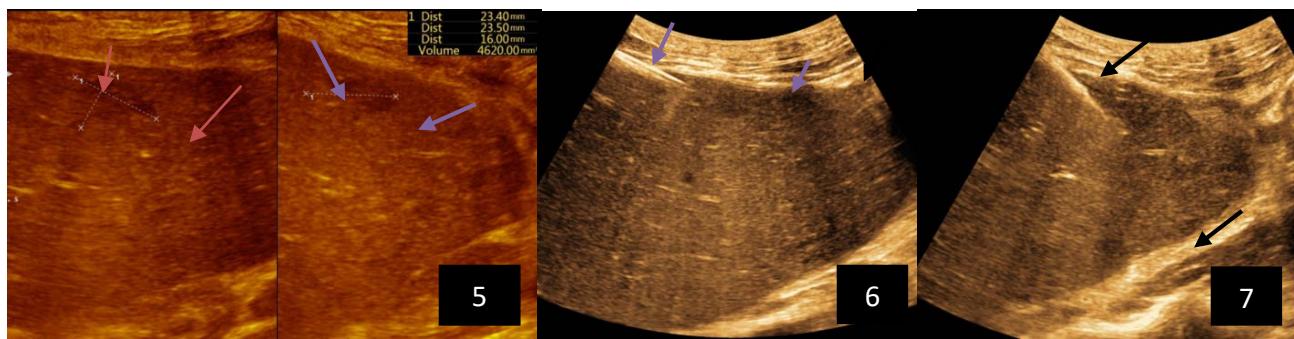

Iconography 1: 54-year-old patient with an intra-splenicsolid mass, anatomopathologically compatible with lymphoma: images 1 and 2: right pleurisy of moderateabundance, image3: celiacadenopathy, image 4: free ascites of moderateabundance, images 5 and 6: intra-splenicsolid mass of around $1418.16\mathrm{ml}$ in B mode and elastographyshowing areas of tumourrigidity, images 7-10: oblique linear images, showingbiopsy gun tracks.

Iconography B: 1 to 4: ultrasound images in mode B showing a large size, 5: ultrasound image in mode B showingsolidhyperechogenic nodules under the capsulorhexis, 6 to 10: ultrasound images in mode B showinglinearhyperechogenic images without overlay in relation to the trajectories of the aiguilles of biopsy.